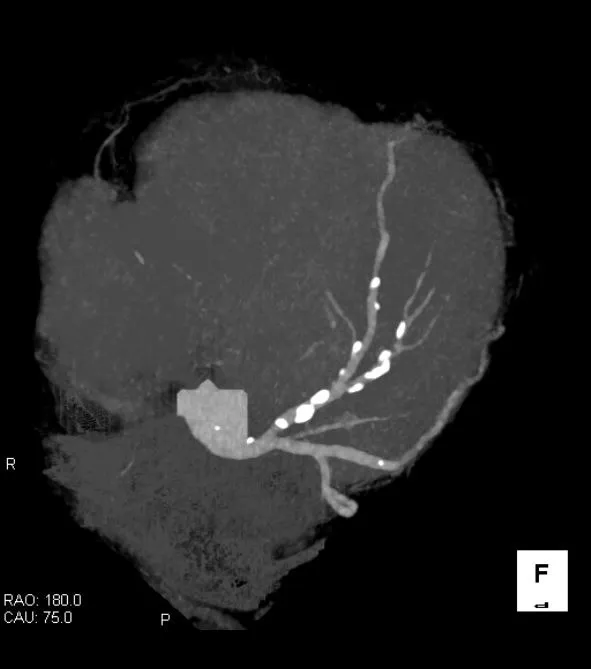

「心臓CT検査」ってなに?と思われるかも知れませんが、基本は心臓を栄養する「冠動脈」を観察するための検査です。

以前は冠動脈がどうなっているか見るためには、カテーテルを用いた血管造影検査が必要でしたが、近年CT装置が発達したため、造影CT検査でも、冠動脈を診ることができるようになったものが「心臓CT検査」です。

「心臓CT検査」では、冠動脈がどのような状態か画像で把握する事ができますので、治療が必要かどうかの判断が容易です。また、冠動脈のどの部分に異常があるのか分かりますので、治療方針の決定にも有用です。冠動脈に異常がなければ、狭心症や心筋梗塞のリスクは非常に低いと考える事が可能です。